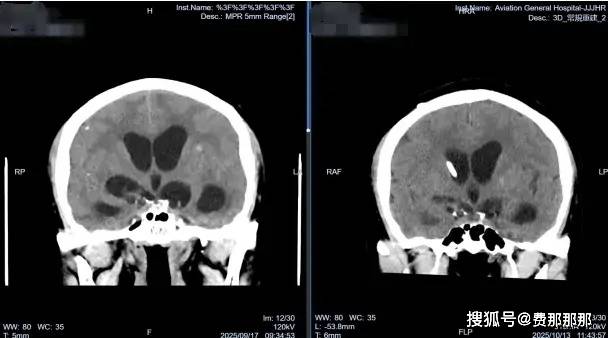

回顾文章开头提到的内蒙古患者图某的情况,他入院后,肖庆教授团队为他做了详细的检查。眼科会诊发现他已有视野缺损和视神经乳突水肿,这表明他的颅内高压已经持续了一段时间,并对视神经造成了损害。他的头颅CT/MR检查显示多发囊性占位,视交叉受压改变,结合他的流行病学史,可以明确脑囊虫病诊断。

术中内镜下可见右侧脑室壁粗糙,广泛炎性黄白色突起肉芽增生——这是既往有过颅内感染的典型表现。肖庆教授更加坚定了之前的判断,进行第三脑室底造瘘,并在基底池内取出数枚囊虫占位,大者外观达2*2cm;同时探查发现基底池内部有多发黄色网状粘连,基底动脉搏动差。